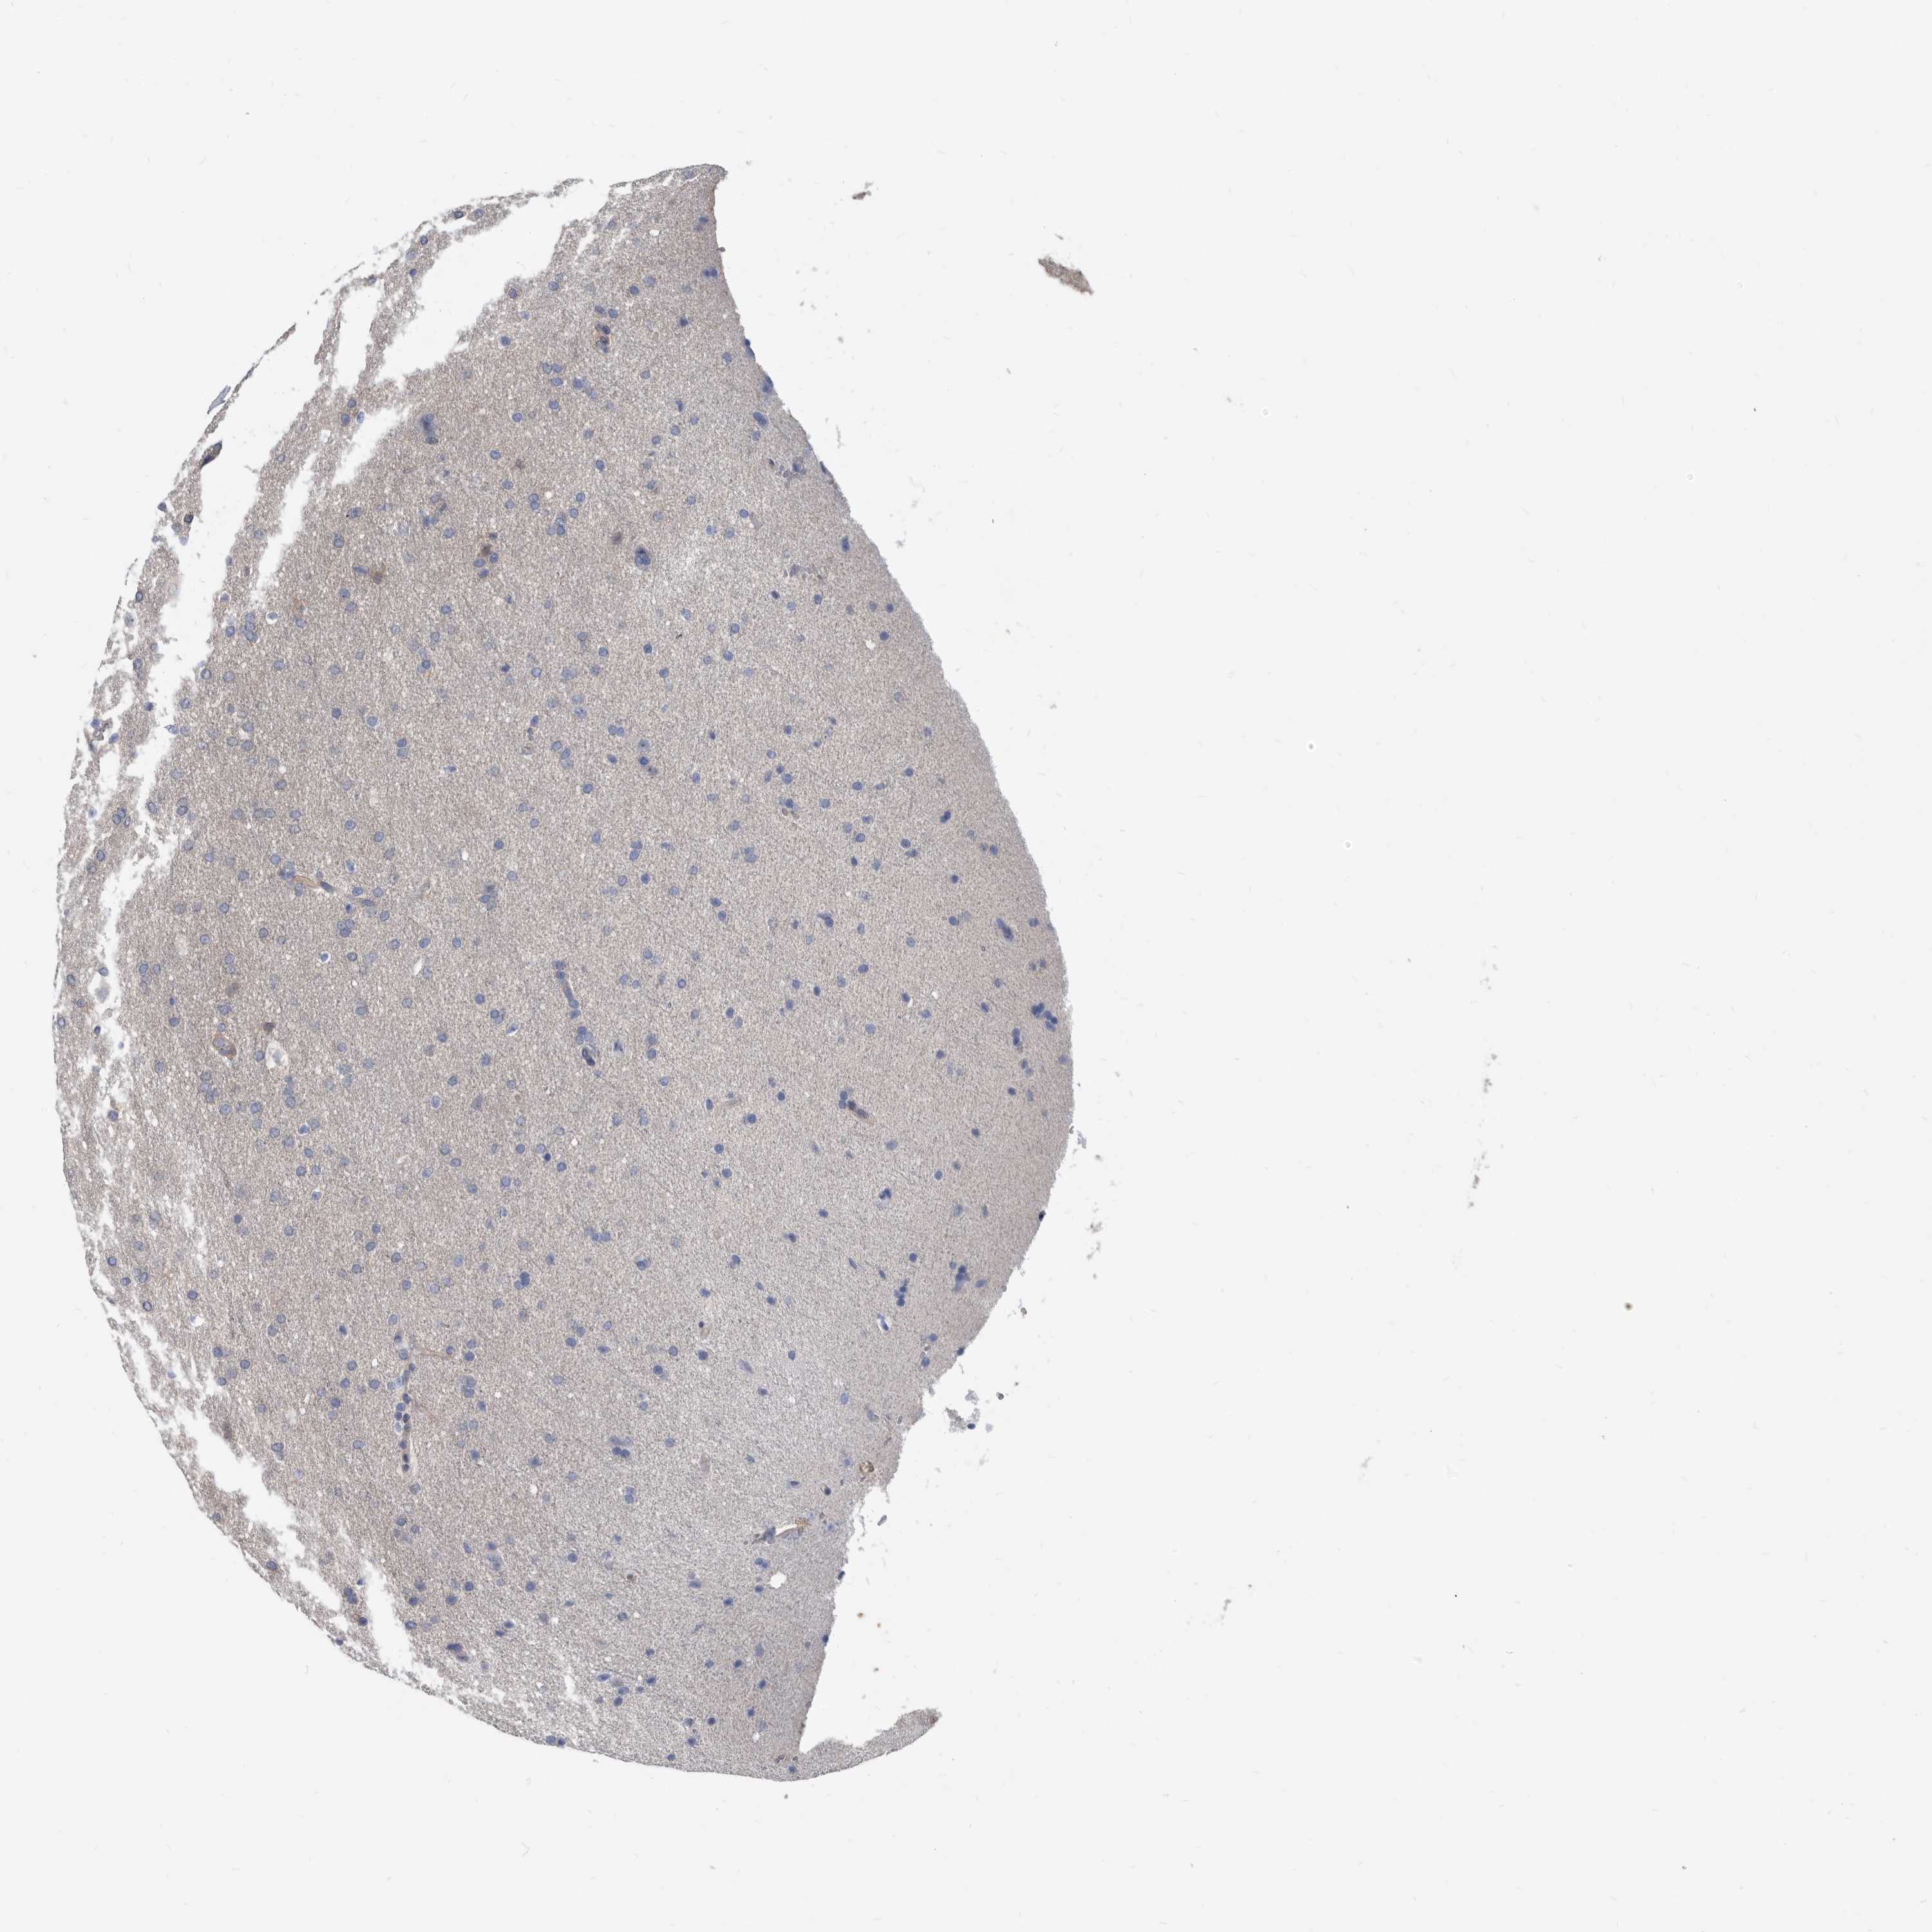

GLIOMA - Protein expressioni

A mouse-over function shows sample information and annotation data. Click on an image to view it in a full screen mode. Samples can be filtered based on level of antibody staining by selecting one or several of the following categories: high, medium, low and not detected. The assay and annotation is described here.

Note that samples used for immunohistochemistry by the Human Protein Atlas do not correspond to samples in the TCGA dataset.

Antibody stainingi

Antibody staining in the annotated cell types in the current human tissue is reported as not detected, low, medium, or high, based on conventional immunohistochemistry profiling in selected tissues. This score is based on the combination of the staining intensity and fraction of stained cells.

Each image is clickable and will lead to virtual microscopy that enables deeper exploration of all samples and also displays staining intensity scores, fraction scores and subcellular localization as well as patient and tissue information for each sample.

Antibody HPA029700

Antibody HPA029701

Antibody HPA029702

Antibody HPA029703

Staining

High

Medium

Low

Not detected

Intensity

Strong

Moderate

Weak

Negative

Quantity

>75%

75%-25%

<25%

None

Location

Nuclear

Cytoplasmic/membranous

Cytoplasmic/membranous,nuclear

Glioma, malignant, High grade

Glioma, malignant, Low grade

Glioblastoma, NOS